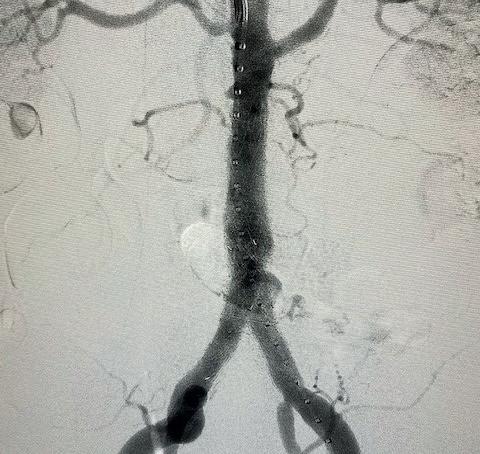

THE PATIENT IS AN 81-YEAR-OLD man with a past medical history of hypertension, hyperlipoproteinaemia, and remote history of smoking, who presents with an expanding saccular abdominal aortic aneurysm (AAA) and severe hip claudication. A preoperative computed tomography angiography (CTA) reveals dense circumferential calcified 90% stenosis of the bilateral common iliac arteries (Figures 1 and 2). In addition, the patient had a mid-aortic highly calcified stenosis. The patient desired a minimally invasive approach and given the underlying conditions, an EVAR was the best option to treat the AAA, as well as the bilateral common iliac artery stenosis.

Preoperative planning focused on three main areas of concern: the first is whether or not the stent graft could advance through the iliacs; secondly, would the stent graft limbs open to nominal diameter within the iliacs; and lastly, whether or not the stent graft would open fully within the AAA.

We used a percutaneous approach. Initially, we were unable to advance the 16Fr DrySeal sheath for the main graft on the right or the 12Fr DrySeal sheath on the left side for the contralateral limb (Figure 3). At this point, we performed IVL with a 7.0x60mm IVL catheter, of both the right and left common iliac arteries. We delivered 150 pulses to each vessel at 4atm and subsequently carefully dilated to nominal pressure of 6atm. Both arteries dilated easily. The Gore Excluder graft was delivered, and the limbs were placed within the common iliac arteries. Post-implantation balloon angioplasty was completed and revealed complete seal of the AAA and no residual stenosis in the iliacs (Figure 4). The patient was found to have a 90% stenosis of the left renal artery, which was treated with a balloon-expandable stent. His postprocedural CT scan revealed a very nice result, a sealed AAA, wide iliac arteries, and no residual stenosis.

Figure 3. Initial intraoperative angiogram

Figure 1. Preoperative CTA revealing dense calcified stenosis of the iliac bifurcation

Figure 4. Completion arteriogram, areas of stenosis completely resolved

Figure

common iliac luminal diameter of 3mm, left common iliac diameter of 5mm